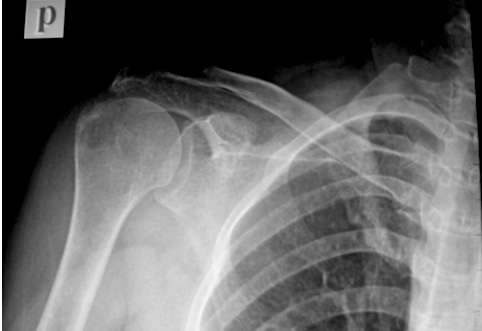

a. X quang thường quy:

-X quang khớp vai thẳng cánh tay tư thế trung tính: Khuỷu gấp 90o. Phim đặt sau vai. Tia tập trung vùng 1/3 dưới khớp vai. Phim này cho thấy củ lớn xương cánh tay, độ dày vỏ xương khoảng lmm, bờ đều, khoang dưới mỏm cùng cánh tay phải lớn hơn 7mm và sự chênh lệch hai bên không quá 2mm.

Hình 7.X-Quang khớp vai thẳng.

Phim cho phép đánh giá sự di lệch lên trên của chỏm xương cánh tay so với ổ chảo, hình dạng củ lớn xương cánh tay, khoảng cách khoang dưới mỏm cùng vai. Trên phim này chỏm di chuyển lên cao, củ lớn xương cánh tay có gai xương và mỏm cùng bị xơ đặc xương.

-XQuang khớp vai thẳng cánh tay tư thế xoay ngoài: tư thế bệnh nhân như trên, xoay ngoài cánh tay. Phim này cho phép phân tích phần trước củ lớn xương cánh tay và bờ của rãnh nhị đầu.

-X-Quang khớp vai thẳng cánh tay tư thế xoay trong: tư thế bệnh nhân như trên ngoại trừ cánh tay xoay trong tối đa. Phim này cho phép phân tích bờ sau củ lớn xương cánh tay là noi bám gân dưới gai và tròn bé, ở phim này khoang dưới mỏm cùng chứa gân dưới gai và tròn bé, nếu khoang này hẹp có nhiều khả năng rách hai gân này.

-X-Quang Y view: xem hình dạng của mỏm cùng vai